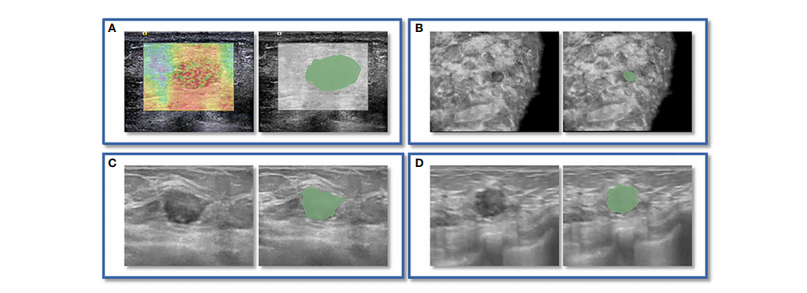

FIGURE 2 An instance of manually delineating a region of interest (ROI). The strain elastography (SE) and automated breast volume scanner (ABVS) images of a 41-year-old female with a solid hypoechoic lesion measuring approximately 16×11×12mm on her left breast. The lesion was irregular in shape, parallel in position, with still well-defined borders, sharp margins, and scattered microcalcifications visible internally, and exhibited no significant posterior echogenicity change or retraction in the coronal plane, and the ultrasound elasticity score was 4, finally, the lesion was classified as BI

RADS category 4a. Pathological examination confirmed it as invasive ductal carcinoma. ROI segmentation was performed on both the SE image (A)and ABVS coronal image (B), with delineation along the boundary of the lesion followed by uniform outward expansion of its edges by 3 mm to

encompass some surrounding tissue.ROI segmentation was performed on ABVS transverse © and sagittal (D) images, respectively, and meticulous

delineation was performed along the lesion’s contour and borders on these two views.

图2手动绘制感兴趣区域(ROI)的示例。这是一位41岁女性的左乳房上有一个约16×11×12mm的实质性低回声病变的应变弹性成像(SE)和自动乳腺体积扫描仪(ABVS)图像。该病变呈不规则形状,位置平行,边界清晰,边缘锐利,内部可见分散的微钙化,冠状位上没有明显的后方声明显改变或回缩,超声弹性评分为4,最终被分类为BI-RADS类别4a。病理检查确认为浸润性导管癌。ROI分割分别在SE图像(A)和ABVS冠状图像(B)上进行,沿病变边界绘制,然后将边缘均匀向外扩展3毫米以包围一些周围组织。ROI分割分别在ABVS横断面(C)和矢状面(D)图像上进行,对这两个视图上的病变轮廓和边界进行了精细细致的绘制